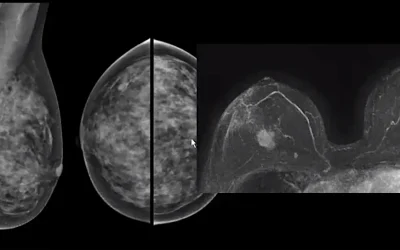

ΚΑΡΚΙΝΟΣ ΤΟΥ ΜΑΣΤΟΥ ΚΑΙ ΜΑΓΝΗΤΙΚΗ ΤΟΜΟΓΡΑΦΙΑ ΜΑΣΤΩΝ

Δεν είναι μόνο μια ροζ κορδέλα, δεν είναι μόνο ο ροζ φωτισμός κτιρίων και μνημείων, δεν είναι μόνο οι ομιλίες και οι διαλέξεις, δεν είναι μόνο ένας Οκτώβριος. Είναι το συνεχές μέλημα αυτοφροντίδας. Αυτό είναι και το μήνυμα των ημερών για τον καρκίνο του μαστού....